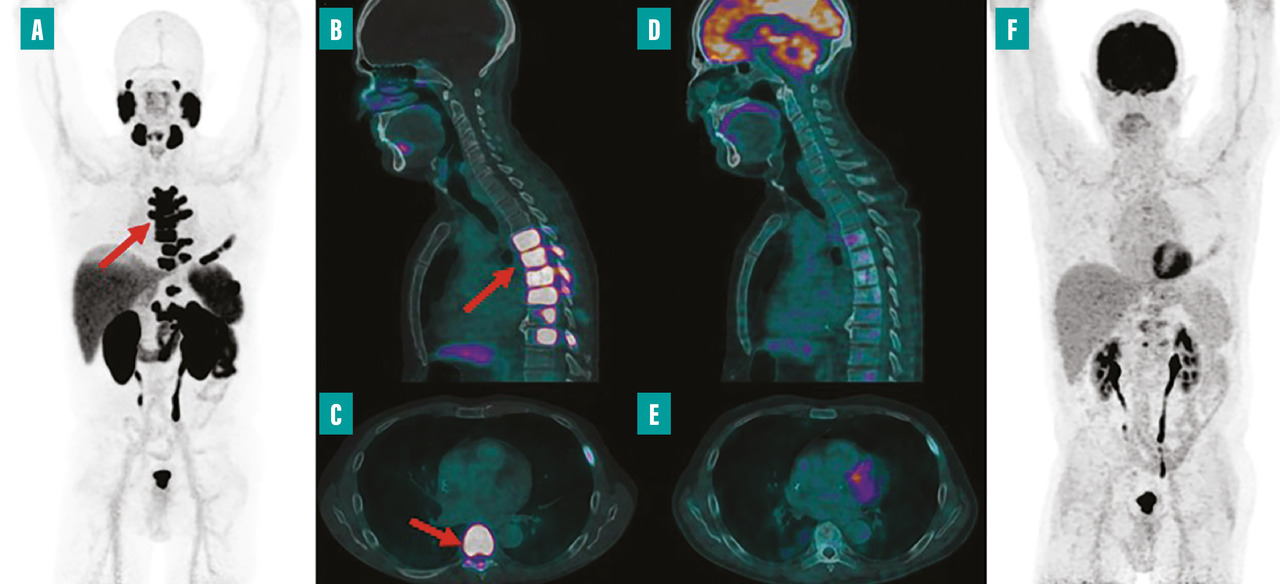

Depuis environ une décennie, des systèmes hybrides alliant TEP et imagerie par résonance magnétique (IRM) sont disponibles en milieu clinique. La TEP-IRM présente l’avantage d’exposer les patients à moins de radiations que la TEP, ce qui est particulièrement bénéfique pour les enfants ou les personnes nécessitant des examens répétés dans le cadre de leur traitement. L’intégration de l’IRM améliore considérablement l’analyse des tissus mous et assure une correspondance spatiale parfaite avec les anomalies fonctionnelles détectées par la TEP. Grâce à sa haute résolution, la TEP-IRM permet d’examiner avec précision les petites structures et de détecter les changements subtils dans les images au cours du traitement. En oncologie, la TEP-IRM est principalement utilisée pour les patients atteints de cancers pelviens (gynécologiques et de la prostate) ainsi que pour les cancers ORL et en neuro-oncologie (fig. 1).9

La médecine nucléaire, depuis ses débuts, a joué un rôle non seulement en imagerie mais aussi en thérapie, notamment grâce à la radiothérapie interne vectorisée (RIV). L’iode 131, utilisé depuis longtemps pour traiter les troubles thyroïdiens, illustre bien cette dimension thérapeutique fondamentale de la discipline. Ce traitement a introduit le concept de théranostique, qui consiste à visualiser précisément la maladie avant de la traiter et ainsi à sélectionner les patients avec le phénotype le plus adapté (ceux avec la plus forte fixation) pour maximiser l’efficacité thérapeutique. Actuellement, la RIV est également appliquée dans le traitement des tumeurs neuro-endocrines et, depuis peu, dans le cancer de la prostate. En effet, en 2023, Pluvicto (lutécium [177Lu] vipivotide tétraxétan) a été approuvé pour le traitement du cancer de la prostate métastatique, résistant à la castration après échec du traitement par hormonothérapie et chimiothérapie (fig. 2).15 Les recherches actuelles examinent l’intégration de la RIV avec des thérapies ciblées et étudient son utilisation en première ligne de traitement.